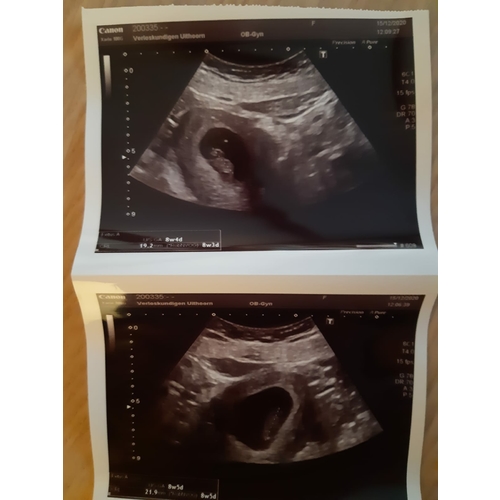

Ik dacht 8 weken te zijn bij de echo ze hadden me alleen iets terug gezet naar 7+4. Nu alweer een goede termijn echo gehad en vandaag alweer 11+4.

Ligt een beetje aan de verloskundige waar je zit. Bij de verloskundige waar ik bij zit is dit een medische echo. De vitaliteits echo. Waar ze kijken of er een gezonde zwangerschap is en of het een een of een meerling is. Dit doen ze vaak tussen de 7 en 9 weken.

Helaas moeilijk tezien gisteren echo gehad ban 8+5 maar mijn baarmoeder ligt nog wat verder naar achter dus niet zn hele helderen echo maar hartje klopt en alles was goed 😍😍